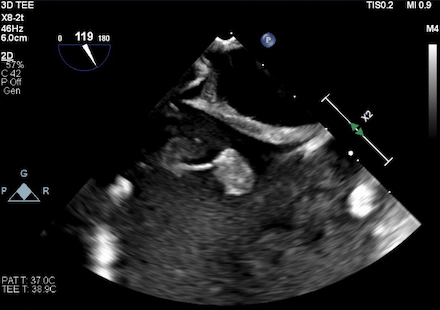

A 36-year-old female with a past medical history of depression, intravenous heroin use, and substance-induced mood disorder presented with altered mental status and respiratory distress. She was found to have methicillin-sensitive staphylococcus aureus (MSSA) bacteremia, a gluteal abscess, multiple septic pulmonary emboli, and a left-sided empyema. She was started on broad-spectrum antibiotics that were narrowed to cefazolin. Her gluteal abscess was drained, and a left-sided chest tube was placed with pleural cultures growing MSSA. TTE demonstrated a mass on the eustachian valve. Subsequent transesophageal echocardiography (TEE) demonstrated two echogenic masses adherent to the eustachian valve, one measuring 17 by 9 millimeters and one measuring 15 by 8 millimeters, consistent with eustachian valve endocarditis. Despite appropriate antibiotic therapy, she continued to have intermittent fevers with persistently positive blood cultures. The patient underwent TEE-guided extraction of the eustachian valve vegetation using the AngioVac aspiration system. TEE at the end of the case demonstrated complete removal of her eustachian valve masses. Blood cultures cleared post-procedure, and she was eventually discharged to acute rehabilitation.